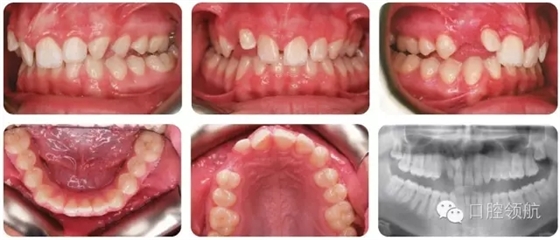

該患者錯(cuò)牙合特點(diǎn)(圖2.38)是什么?

● II類2分類切牙關(guān)系。

● 覆牙合較深。

● 中線不調(diào)(上中線右偏2mm)。

● 后牙近中尖對(duì)尖關(guān)系(雙側(cè))。

● 上牙弓中度擁擠。

● UR3未萌,可能與UR2異位。